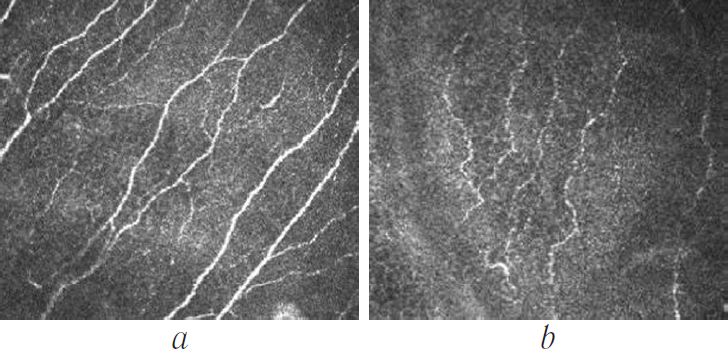

Therefore, patients with PEX had a significant increase in the number of nerve branches per mm2 after PHACO (p = 0.0001; Fig. 5). The remaining parameters did not significantly differ between the groups.

Fig. 5. Tortuosity of subbasal nerve plexus: а – in control group; b – in PEX group

Granular changes in nerve cells were observed in both groups; however, the experimental group showed significantly more pronounced changes before and after PHACO. Mean score before PHACO was 2.1 and 1.1 in the study and the control groups, respectively, compared to 2.4 and 1.3, respectively, after PHACO (p = 0.03 and p = 0.04, respectively; Fig. 6).

Fig. 6. Subbasal nerve plexus: а – in control group; b – in PEX group